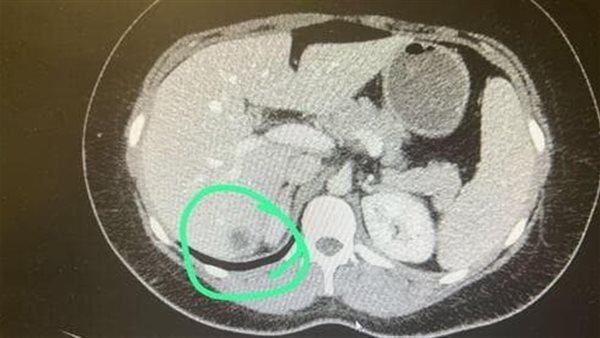

وكشفت الأشعة المقطعية فقط عن نتيجة خطيرة وهى ان الحمل في كبد المرأة، والتي تم تأكيدها لاحقًا على أنه جنين في الأسبوع الثامن.

أصيب الأطباء بالصدمة في إسرائيل عندما اكتشفوا ان سيدة حامل في الثلاثينيات من عمرها وكيس الحمل يوجد في الكبد وعمر الجنين 8 أسابيع ، كما أذهل الفحص بالموجات فوق الصوتية الاطباء المخضرمين في مركز بيلينسون الطبي وكان عليهم أن سقوموا بإجراء عملية لإنهاء الحمل بسبب الخطر على حياتها.